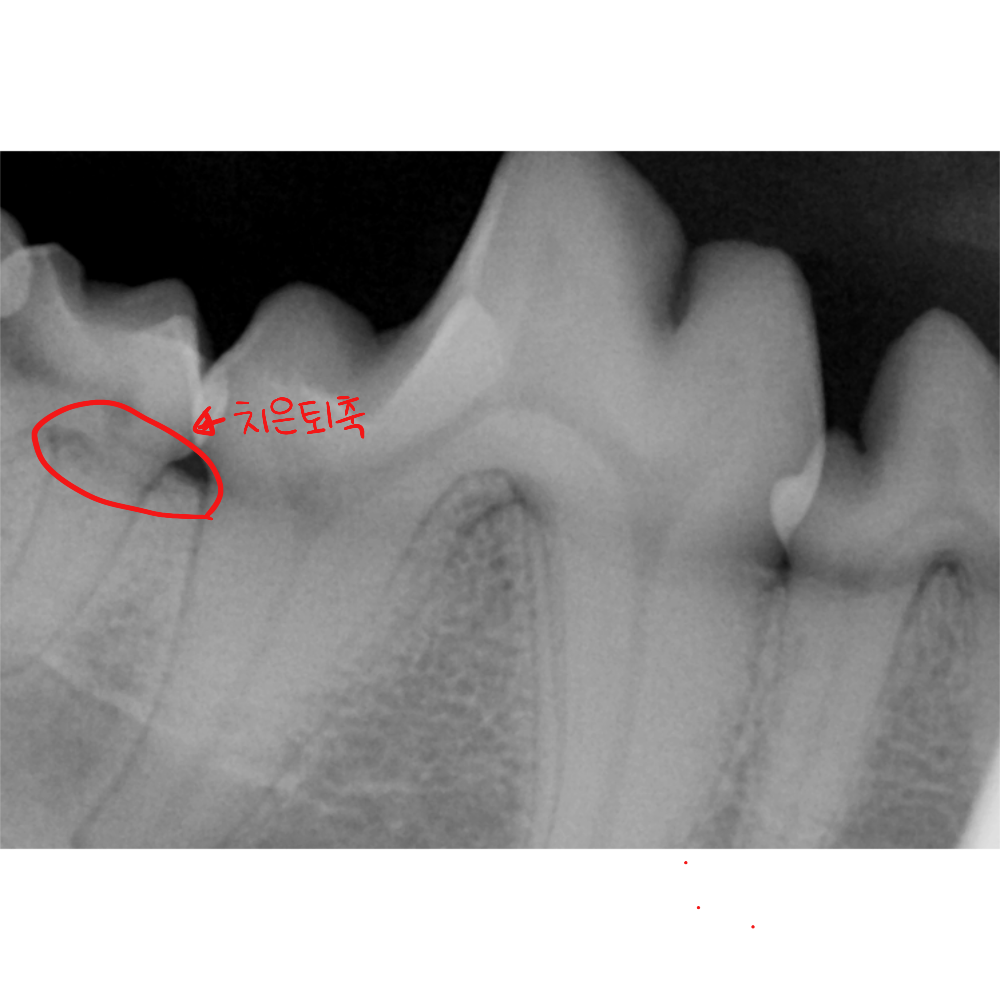

2. 구강 엑스레이를 통한 치조골 분석

발치 여부를 결정하는 가장 중요한 기준은 구강 엑스레이입니다. 치아 뿌리를 감싸고 있는 치조골의 높이가 얼마나 유지되고 있는지를 확인해야 합니다.

검사 결과, 해당 부위의 치조골 높이는 정상 범위 내에 있었고 뿌리 끝까지 진행된 골 소실은 관찰되지 않았습니다. 치아를 지탱하는 기반 구조가 유지되고 있다는 의미입니다.